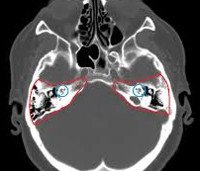

Диагностическая процедура обычно рекомендуется нейрохирургами, травматологами, челюстно-лицевыми хирургами и отоларингологами. С помощью компьютерной томографии височных костей выявляются переломы, аномалии развития, воспалительные и инфекционные процессы различного происхождения и локализации (в области внутреннего и среднего уха, сосцевидного отростка ). Тест показан при подозрении на опухоли височной кости. Метод позволяет определить размер, форму и частоту возникновения рака (доброкачественного или злокачественного), выявить наличие метастазирования опухоли в другом месте.

КТ дает возможность оценить тяжесть остеосклероза, подтвердить наличие и тяжесть деструкции при распространении гнойных процессов на костные структуры и определить причину оттока из наружного слухового канала. Компьютерная томография височной кости исследует близлежащие мягкие ткани. Процедура проводится на этапе предоперационной подготовки к установке кохлеарного имплантата.